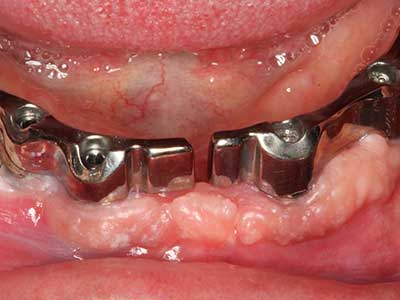

Fig. 14: Placement of four tapered RSX implants (Bego Implant Systems, Bremen).

Fig. 15: The one-year follow-up x-ray examination shows stable conditions at the bone level.

Fig. 16: The intraoral conditions are also stable with embedding of the implants in keratinized gingiva.